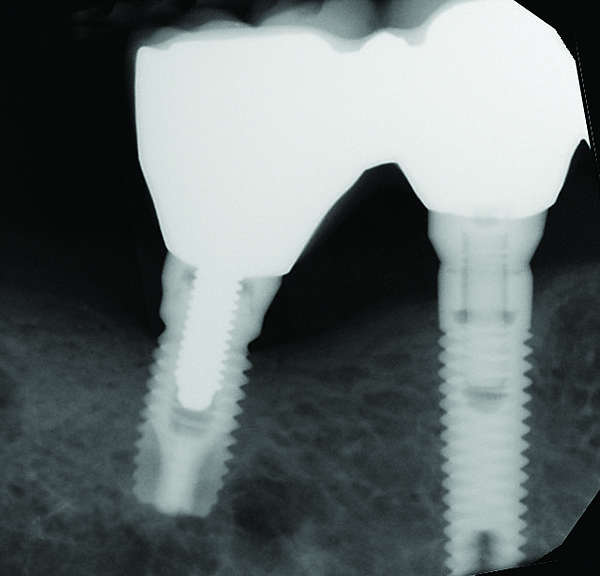

Fig 16 and Fig 17. Clinical photographs demonstrating bone loss and recession 20 years after prosthesis insertion. Initially the gingival margin covered the implant collars and threads. Fig 16: maxillary right; implants were placed at site Nos. 3 through 6. Fig 17: maxillary left; implants were placed at site Nos. 10 through 13.